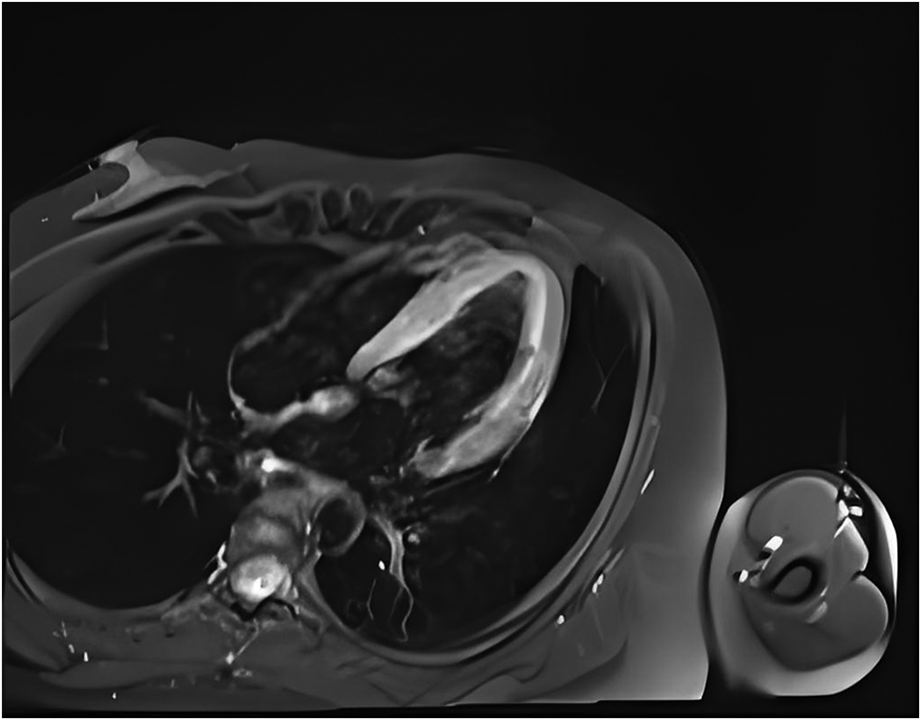

One day after admission, the patient's vital signs were unstable and her blood pressure remained low despite high doses of norepinephrine and m-hydroxyamine. Physical examination revealed scattered red maculae and maculopapules on the trunk and limbs, accompanied by iridoid lesions, blisters, and oral mucosal erosion (Figure 2). Echocardiography examination indicated a significant decrease in Ejection fraction (24%). A review of laboratory tests showed: WBC 6.6 × 109/L, CRP 20.2 mg/L, ALT 225 U/L, LDH 658 U/L, cTnI 20.9 ng/ml, CK 803 U/L, Lactate 6.62 mmol/L, NT-proBNP 6,690 ng/L. Considering the risk of cardiac arrest remains high, endotracheal intubation, V-A ECMO, and emergency coronary angiography were performed. Coronary angiography showed no obvious coronary vessel stenosis (Figure 3). At the same time, we performed extensive hematological tests to determine the cause of the erythema multiforme. Blood cultures were negative for bacteria and fungi. Immunological tests such as antinuclear antibodies, anti-double-stranded DNA antibodies and rheumatoid factors were negative. COVID-19 polymerase chain reaction was negative. HIV, Hep A, B, C and Treponema pallidum serologies were negative. Coxsackie virus, adenovirus, influenza A virus, influenza B virus, human parainfluenza virus, respiratory syncytial virus, Mycoplasma pneumoniae, chlamydia pneumoniae were negative. However, Chemiluminescence showed that herpes simplex virus-1 (HSV-1) was positive. Therefore, we considered that the patient had severe myocarditis and erythema multiforme due to infection with HSV-1 virus. We gave acyclovir needle antiviral and methylprednisolone needle anti-inflammatory. After the initiation of ECMO, the patient's blood pressure significantly increased and gradually stabilized at a systolic blood pressure of 90–168 mmHg and a diastolic blood pressure of 64–112 mmHg. Arterial blood gas analysis showed a significant improvement in acidosis. Therefore, we discontinued all vasoactive medications on the second day following the initiation of ECMO. Four days after the initiation of ECMO, the flow rate was reduced to 1.2 L/min, the patient's blood pressure remained relatively stable, blood gas analysis indicated good tissue perfusion, and follow-up echocardiography showed that the ejection fraction (EF) had recovered to 42%. We concluded that the criteria for ECMO withdrawal had been met, and ECMO was removed four days after its initiation. The day after ECMO was removed, the patient was then scheduled for a cardiac magnetic resonance imagery (CMRI) examination. Cardiac magnetic resonance T2-weighted imaging shows diffuse hypersignal in the left ventricular wall (Figure 4). Finally, the patient's symptoms gradually improved, the rash gradually disappeared on the seventh day, and she was discharged successfully after 2 weeks of treatment. The specific clinical process is shown in Supplementary Image 1. The patient has now been under observation for a period of one year, during which time she has attended five outpatient reviews at the hospital. No significant abnormalities have been observed in the patient's skin, troponin levels, electrocardiogram, or cardiac ultrasound. Furthermore, the patient has not continued any medications for the treatment of ring erythematosis or myocarditis.

Figure 4

Cardiac magnetic resonance T2-weighted imaging shows diffuse hypersignal in the left ventricular wall.

Myocarditis, one of the most important diseases of cardiovascular disease, used to have an incidence of 1 to 10 cases per 100,000 people per year (9). The highest risk was found in people aged 20 to 40 (10). Myocarditis can be caused by a variety of infectious and non-infectious causes. In infectious myocarditis, viruses are the most common cause. Viral myocarditis can be caused by adenovirus, enterovirus, COVID-19 and other viruses, but HSV-1 virus caused myocarditis is extremely rare. Bowles et al. used polymerase chain reaction (PCR) to analyze viral genomes in heart tissue and blood to identify common viral causes of myocarditis in different age groups. The viral genome was amplified in 239 (38%) of 624 patients with myocarditis, of which HSV infection accounted for only 0.8% of myocarditis (5). Previous basic studies have shown that myocarditis caused by HSV-1 infection is regulated by members of the TRIM protein family. TRIM29 could regulate the innate immunity to promote DNA virus HSV-1 infection (11) and loss of TRIM29 mitigates viral myocarditis by attenuating PERK-driven ER stress immune response (12). Additionally, TRIM18 deficiency is reported to control DNA virus HSV-1 infection and viral myocarditis (13). In this case, although acute myocardial infarction caused by coronary artery occlusion was excluded by coronary angiography, and myocarditis was diagnosed by troponin, magnetic resonance, and echocardiography, it was still difficult to diagnose the cause of myocarditis. The occurrence of multitype erythema provides the basis for the diagnosis of viral myocarditis and the direction for the targeted virus screening.